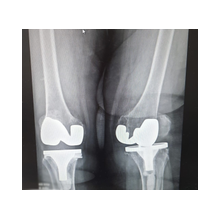

Aşınmış, hasar görmüş ya da eklem yüzeyleri tamamen bozulmuş diz ekleminin, yapay bir eklemle değiştirme işlemidir. Ameliyatta, ağrıya neden olan hasarlı kemik ve kıkırdak dokular çıkarılarak; yerine metal ve özel plastikten yapılmış, uzun ömürlü bir protez yerleştirilir. Bu sayede diz, tekrar ağrısız ve stabil bir şekilde çalışır hale gelir.

Eklem yüzeyleri özel kılavuzlar yardımı ile temizlendikten sonra metal protez eklem yüzeylerine bir kemik çimentosu ile adapte diyoruz. Bu iki metal yüzeyin sürtünmesini azaltmak için polietilenden yapılmış özel bir plastik tabakayı sisteme dahil ediyoruz.